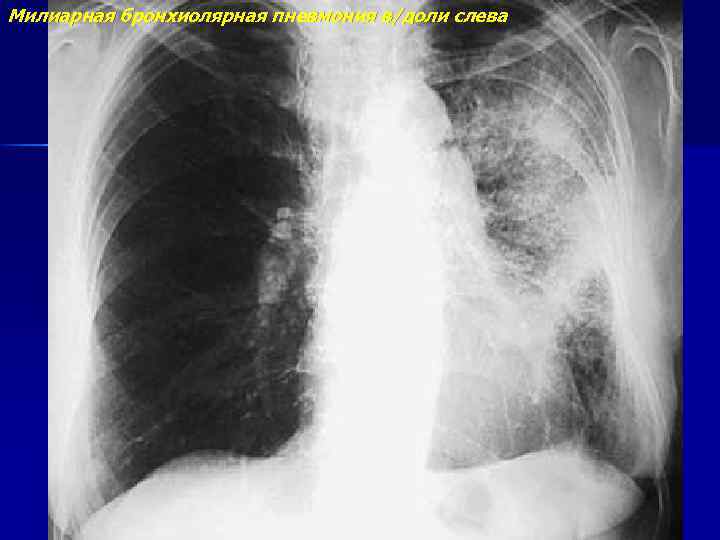

Милиарная бронхиолярная пневмония в/доли слева